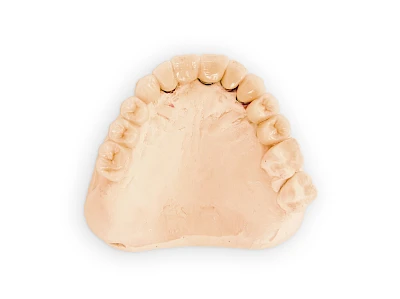

Implantate sind künstliche Zahnwurzeln. Nach einer gewissen Einheilzeit im Knochen (meist 3-6 Monate) erfolgt über einen separaten Aufbau (Abutment) die Befestigung einer Krone bzw. Brücke oder Zahnprothese.

Implantate: Bestandteile

Implantate: Kronen & Brücken

Fehlen einzelne Zähne und die Nachbarzähne sind unbeschadet oder gut zahnärztlich versorgt, werden immer häufiger Implantate gewählt, um die Lücken zu schließen. Auch bei größeren oder verteilten Lücken, wenn keine herausnehmbare Prothese gewünscht ist, werden Implantate für Kronen- bzw. Brückenversorgungen gesetzt. In Einzelfällen entscheiden sich sogar zahnlose Patienten für eine festsitzende Versorgung auf Implantaten.